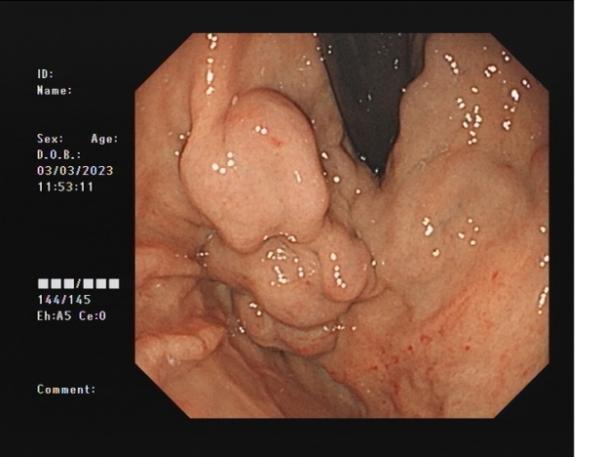

胃底靜脈曲張 內鏡下組織膠粘合術

胃底靜脈曲張組織膠粘合術(HI):治療胃底食管靜脈曲張,防止靜脈曲張破裂出血,降低因肝硬化導致胃底靜脈曲張破裂引起的致命風險。